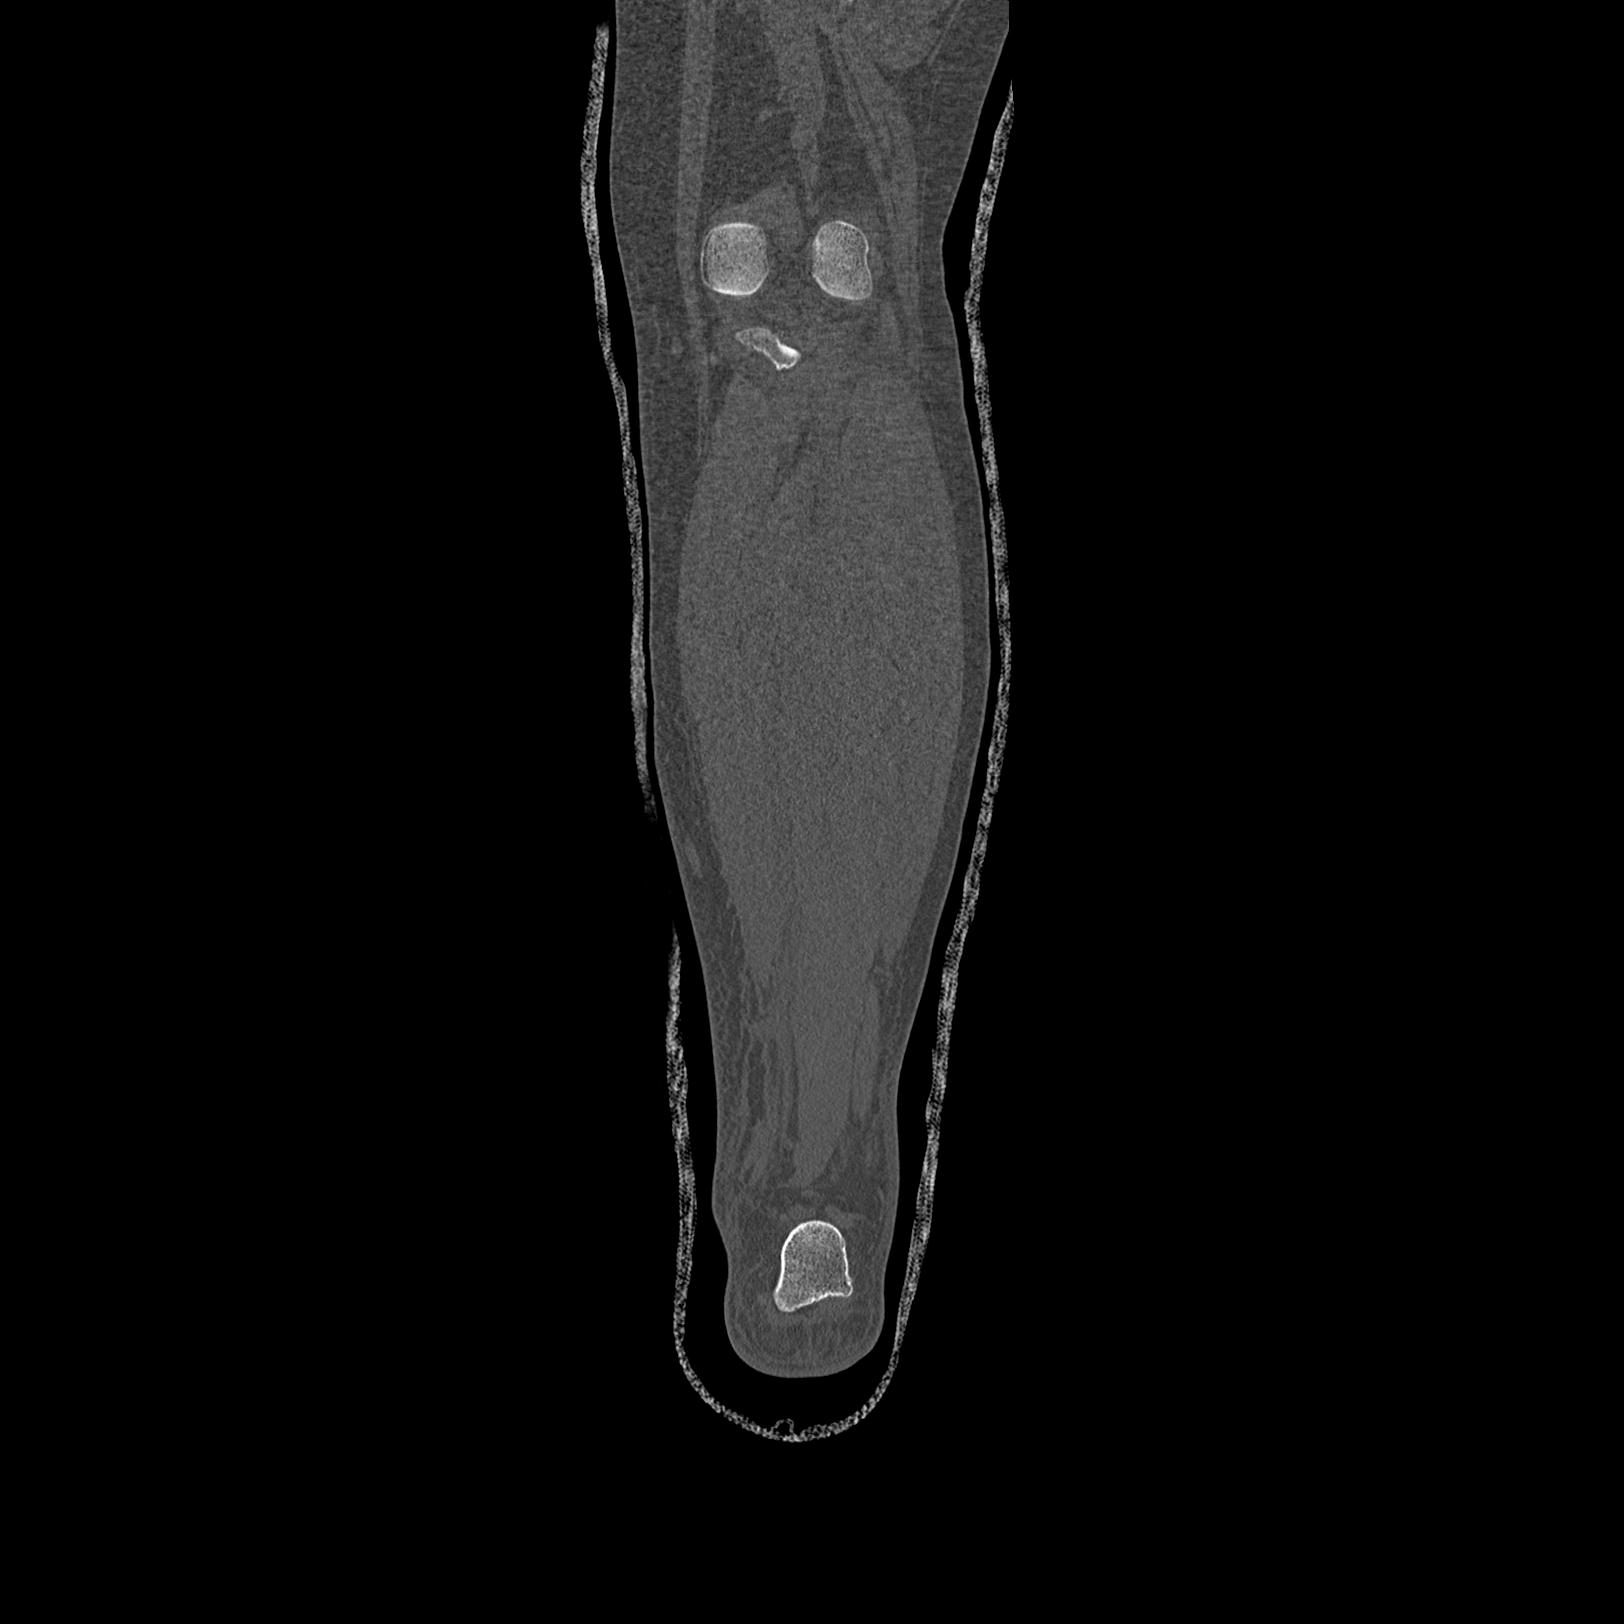

症例写真集

102803 1/12(キウスなし) 1/27 左下腿 4R 30歳女性 左脛骨軸内釘